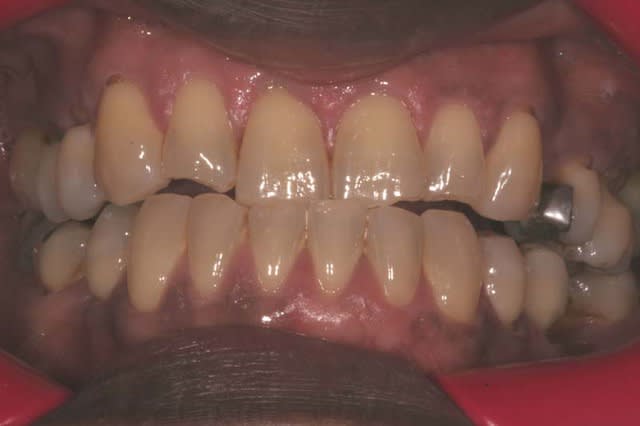

DEPART

1 exdxj8 - Eugenol

le patient peut se mettre en bout à bout incisif

2 qvgxxz - Eugenol